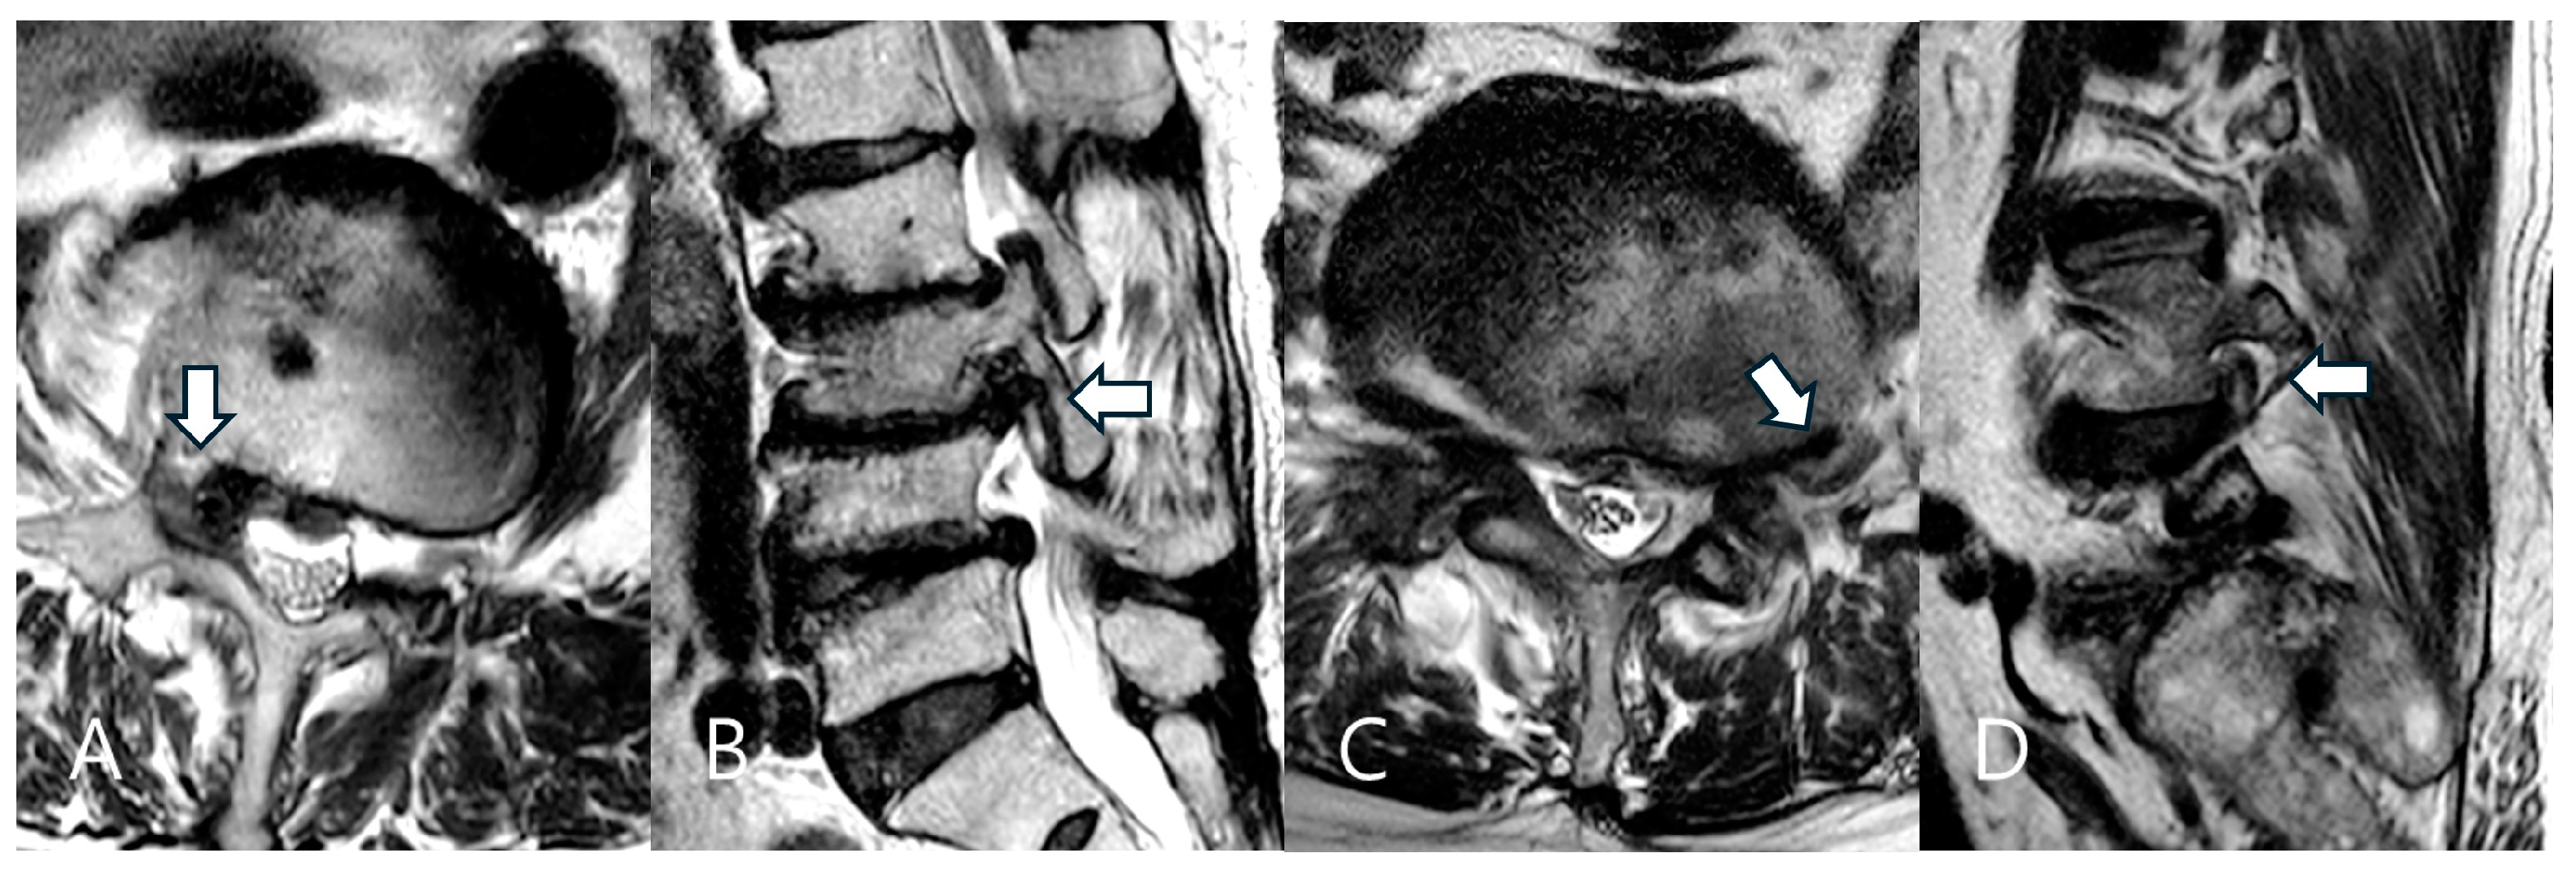

- Lee, S.; Lee, J.W.; Yeom, J.S.; Kim, K.J.; Kim, H.J.; Chung, S.K.; Kang, H.S. A practical MRI grading system for lumbar foraminal stenosis. Am. J. Roentgenol. 2010, 194, 1095–1098. [Google Scholar] [CrossRef]

- Park, H.J.; Kim, S.S.; Lee, S.Y.; Park, N.H.; Rho, M.H.; Hong, H.P.; Kwag, H.J.; Kook, S.H.; Choi, S.H. Clinical correlation of a new MR imaging method for assessing lumbar foraminal stenosis. Am. J. Neuroradiol. 2012, 33, 818–822. [Google Scholar]